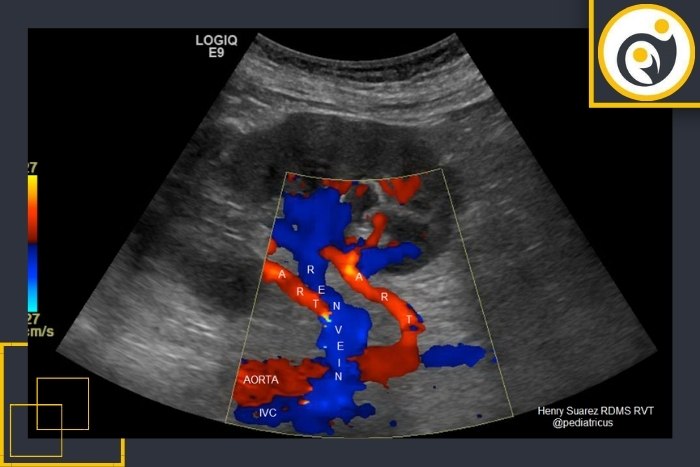

سونوگرافی داپلر یکی از دقیق‌ترین روش‌های تصویربرداری برای بررسی وضعیت کلیه پیوندی است. این روش بدون نیاز به تزریق ماده حاجب و بدون خطر برای بیمار انجام می‌شود و هدف آن ارزیابی جریان خون در شریان‌ها و وریدهای کلیه پیوندی است.

در آغاز بیمار روی تخت معاینه دراز می‌کشد و پزشک متخصص یا کارشناس سونوگرافی ژل مخصوصی را روی ناحیه شکم در محل کلیه پیوندی قرار می‌دهد. سپس با استفاده از پروب دستگاه تصویر کلیه روی مانیتور نمایش داده می‌شود. در این مرحله حالت داپلر فعال می‌شود تا حرکت خون در عروق مختلف کلیه قابل مشاهده باشد.

در بررسی داپلر پزشک به جهت و سرعت جریان خون در شریان کلیوی، ورید کلیوی و شاخه‌های کوچک‌تر توجه می‌کند. هرگونه کاهش، انسداد یا برگشت جریان خون می‌تواند نشانه‌ای از تنگی، لخته یا اختلال در عملکرد کلیه باشد. شاخص مقاومت عروقی (RI) نیز از جمله پارامترهای مهمی است که در گزارش ثبت می‌شود و تغییرات آن می‌تواند نشانه‌ای از رد پیوند یا التهاب باشد.

در داپلر رنگی جهت و شدت جریان خون با رنگ نمایش داده می‌شود در حالی‌که داپلر طیفی نمودار سرعت و نوع جریان را به‌صورت گرافی نشان می‌دهد.